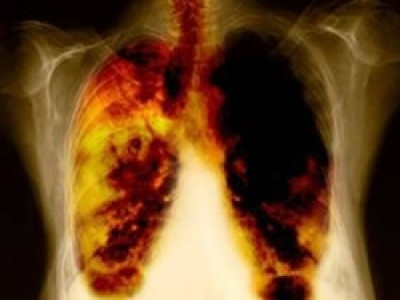

Phổi

Đây là cơ quan thuộc hệ thống đường hô hấp, dễ bị tổn thương nhất. Phổi chịu tác động lớn của môi trường sống, và các hoạt động sinh hoạt hàng ngày của bạn.

Ung thư phổi là căn bệnh thường gặp nhất, đặc biệt là nam giới. Theo thống kê thì có tới 90% bệnh nhân mắc ung thư phổi có liên quan đến thuốc lá.

Ngoài thuốc lá thì tác động của môi trường sống cũng là một nguyên nhân lớn khiến bạn mắc ung thư phổi. Khói bụi, ô nhiễm môi trường, hóa chất độc hại cũng có tác động lớn đến phổi của bạn.

Do đó, hãy sử dụng đồ bảo hộ khi tiếp xúc với môi trường khói bụi, không hút thuốc lá, tránh xa khu vực có khói thuốc để bảo vệ phổi của bạn.